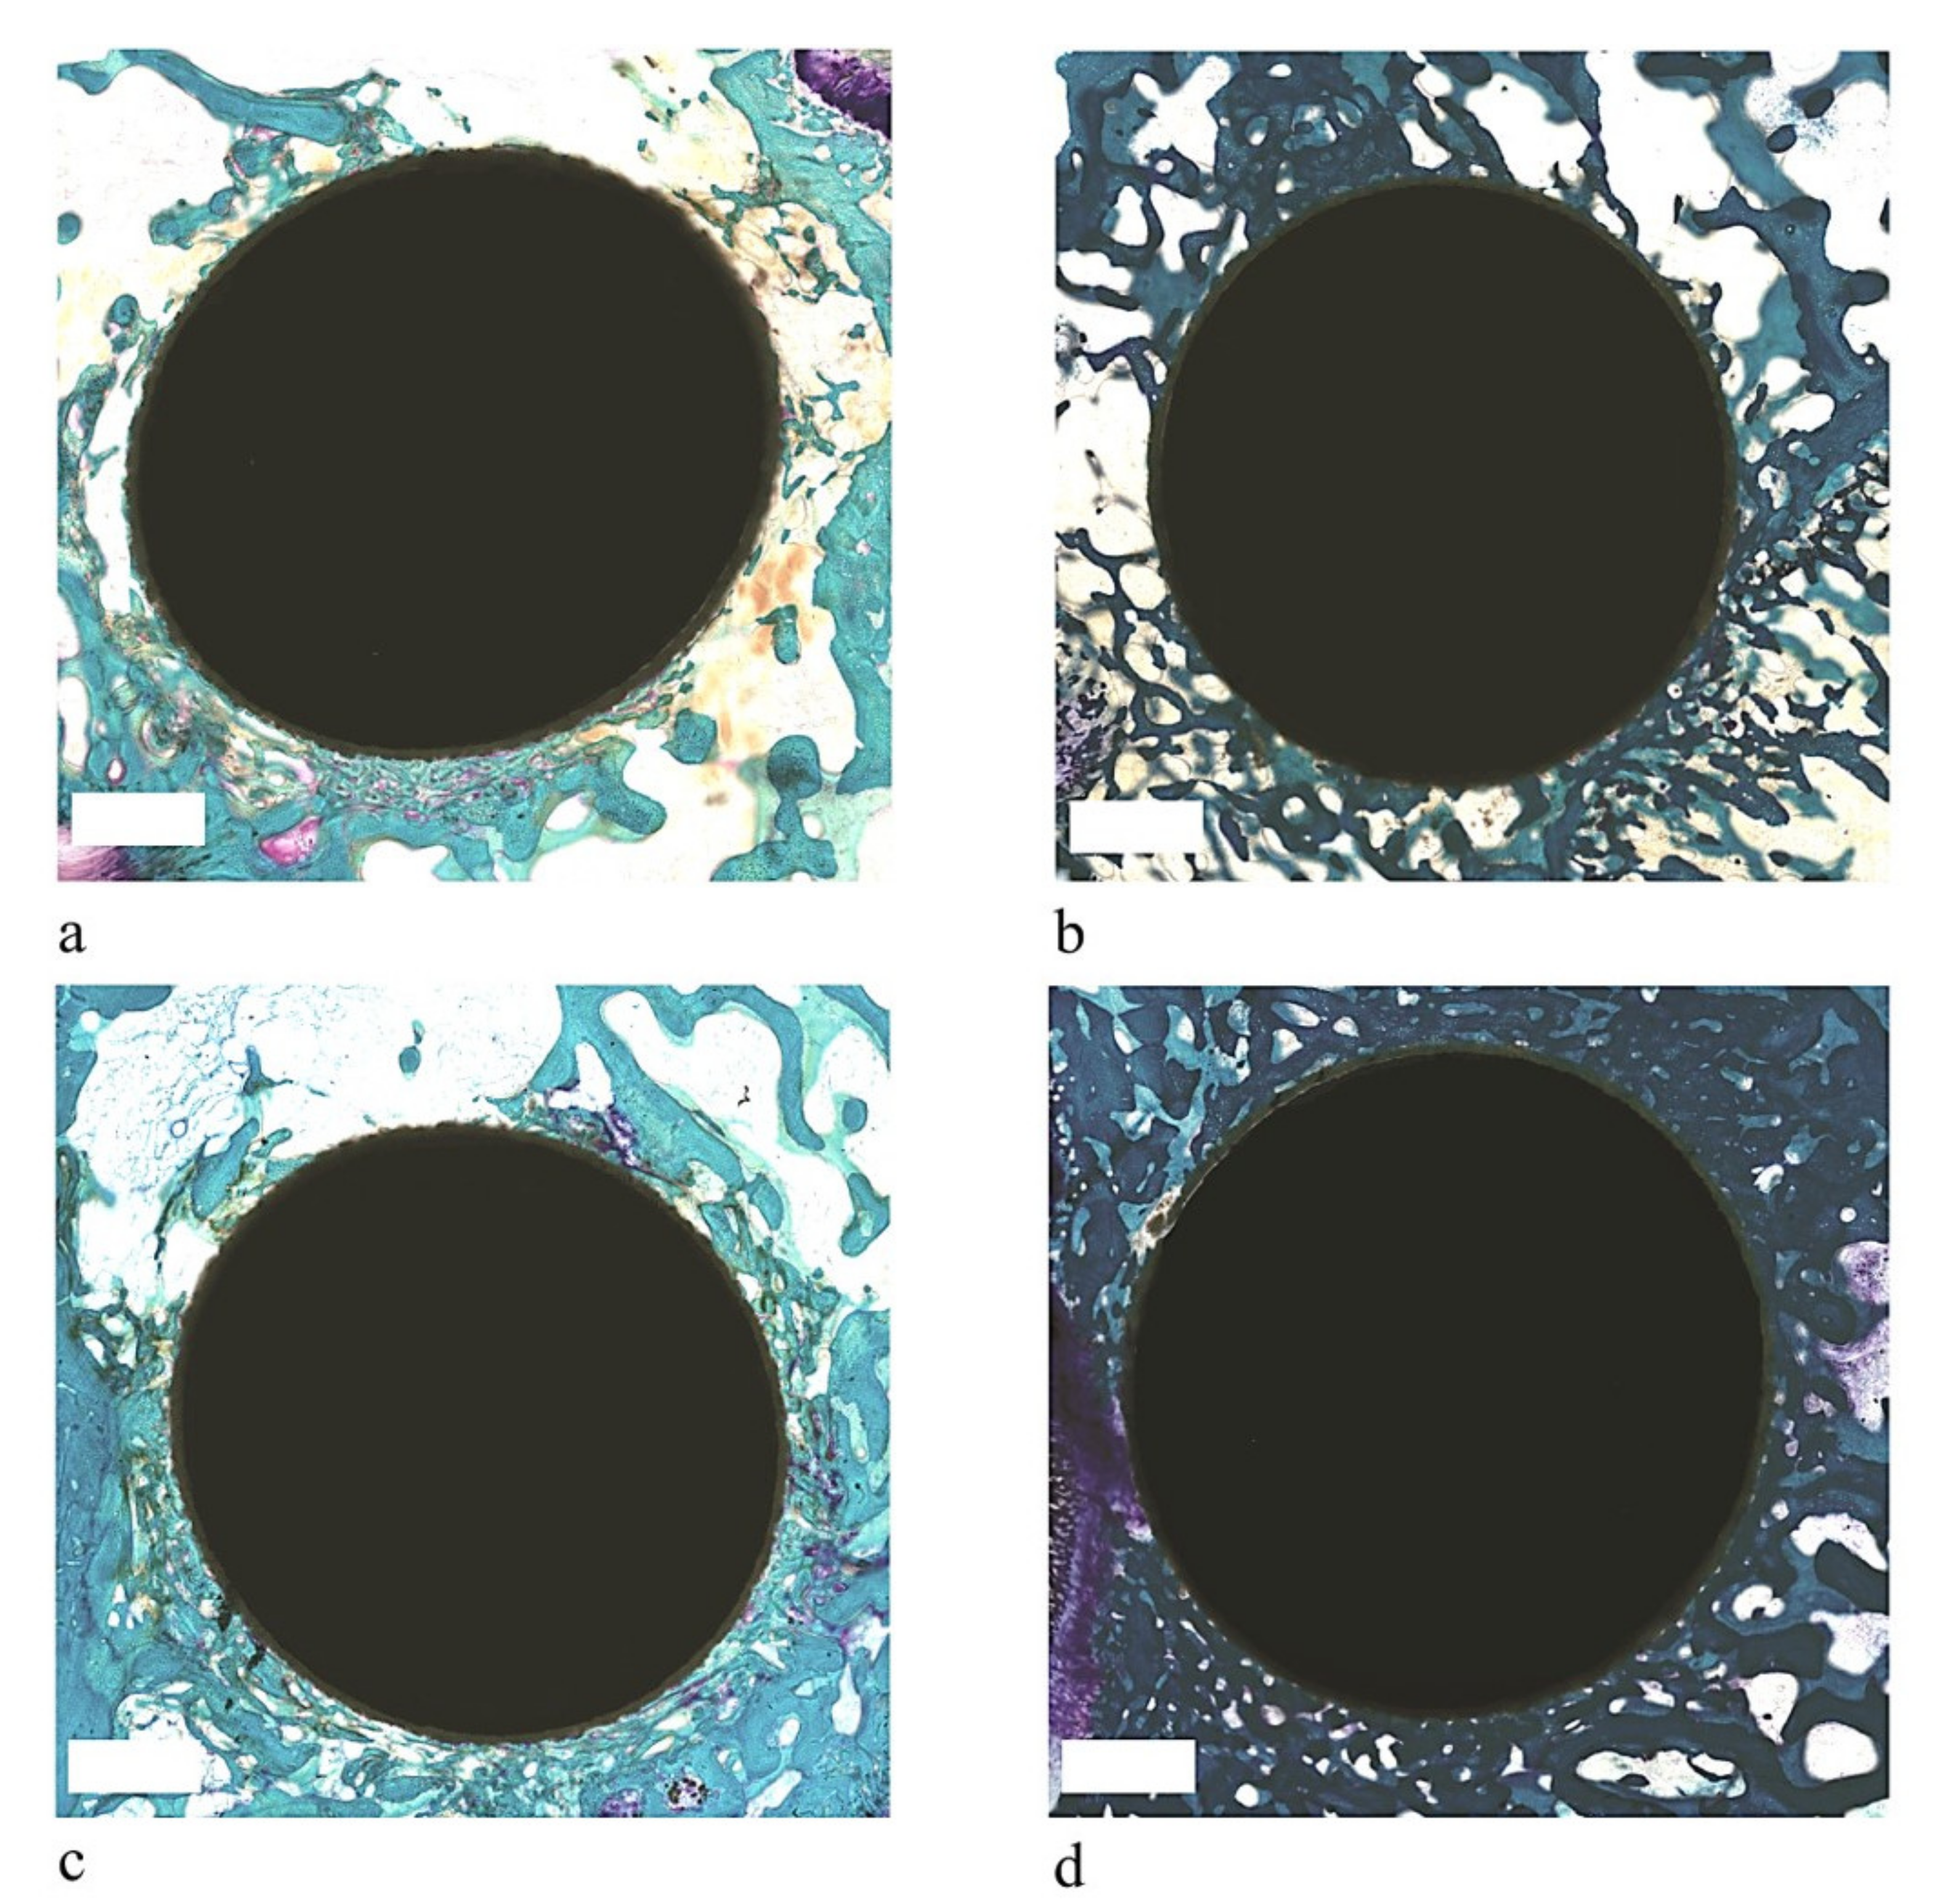

3.2. Histology